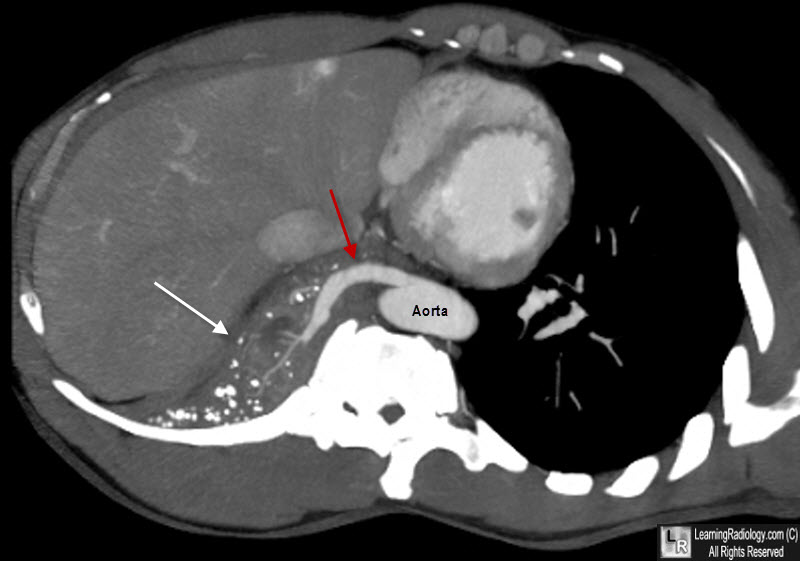

CXR, CT

MRA/혈관조영술: 비정상 혈액 공급 확인

정의: 정상 bronchial tree와 연결되지 않은 폐조직 덩어리의 존재, 대동맥 등 체순환계에서 비정상적인 혈액 공급을 받음